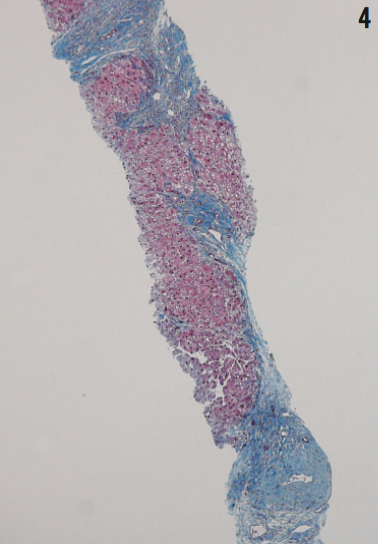

A day before discharge, the girl underwent a bone marrow biopsy and transjugular liver biopsy with hepatic venous wedge pressure measurements. The results of the liver biopsy showed differential hepatic venous pressure of 9 mmHg, which signified mild portal hypertension. Liver biopsy results also revealed histologic findings consistent with extensive hepatic fibrosis and early cirrhosis (Figure 4). Bone marrow biopsy results showed hypocellularity and 100% donor engraftment; further evaluation revealed negative results for viral causes of bone marrow failure. When the patient was assessed 2 weeks after the initial evaluation, her levels of liver transaminases were within reference range.

Dyskeratosis congenita presentation varies significantly from one patient to another, but in the case of our patient, nail dystrophy and oral leukoplakia were the signs that led to the diagnosis. In some cases, dyskeratosis congenita can present with impaired proliferation of hemopoietic stem cells leading to aplastic anemia and bone marrow failure. In addition, loss of telomerase function can be associated with pulmonary fibrosis as well as dyskeratosis of skin and nails. Idiopathic liver cirrhosis presenting as portal hypertension has been described in a few cases, and other cases include reports of dental anomalies, genitourinary abnormalities, osteoporosis, and ophthalmic manifestations.3,4